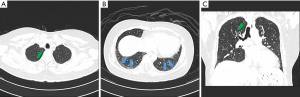

The hematological workup revealed normal full blood count parameters. The hemoglobin level was 12.6 g/dL, the white blood cell count was 7.7×109/L, and the platelet count was 382×109/L. However, the erythrocyte sedimentation rate (ESR) and C-reactive protein (CRP) levels were elevated at 44 mm/h and 7.5 mg/L, respectively. The results of the liver function, kidney function, and urinalysis tests were all unremarkable. Autoantibody testing detected rheumatoid factor (RF) at 40 IU/mL, anti-cyclic citrullinated peptide (anti-CCP) at 60.2 U/mL, anti-DNA topoisomerase I (Scl-70) antibodies, and anti-Ro (SS-A) antibodies. X-rays of bilateral hands revealed subchondral sclerosis of both distal radii with mild joint space narrowing of both radiocarpal joints as shown in Figure 1.

Therefore, the diagnosis of RA and suspected SSc was initially made in primary care. She was subsequently referred to a rheumatologist, and the diagnosis OS involving RA and SSc was confirmed. The patient was initially prescribed methotrexate (MTX) tablets at a dosage of 10 mg per week and diclofenac tablets at 50 mg as needed. Later, hydroxychloroquine 200 mg once daily (OD) and sulfasalazine 500 mg twice daily were also added to control disease activity.